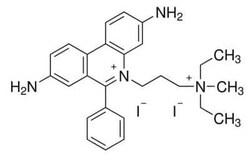

Novus Biologicals™ Propidium Iodide